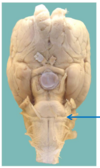

6. rostral/caudal neuropore = pt closed to (hole) - get smaller + smaller + close last

from subarach space: 1. where enlarged form cerebellomedullary cistern @ atlanto-occipital junction 2. where widens beyond end spinal cord form lumbar cistern (L5-6 space) via cisternal puncture

atlas